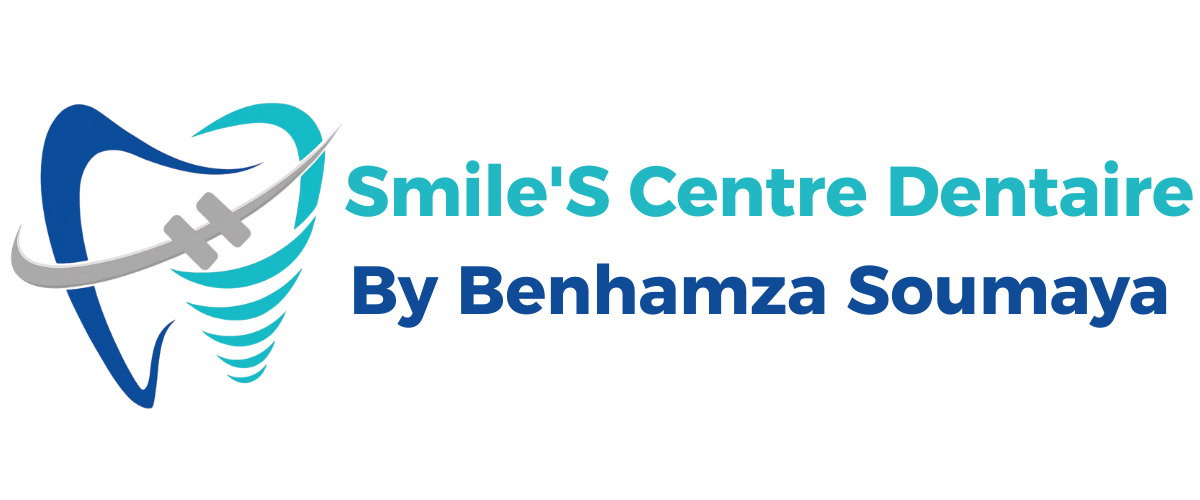

Lorsqu’une carie atteint la pulpe dentaire, un traitement endodontique (traitement de canal) est nécessaire.

Grâce à une technologie de microscopie et des instruments modernes, le Dr. Soumaya BenHamza nettoie et scelle le canal avec une précision exceptionnelle, permettant à votre dent de rester en place et de fonctionner normalement.